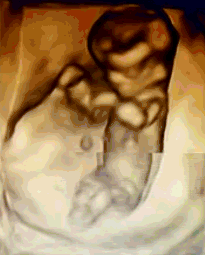

NT是胎儿颈部半透明膜的缩写,是10~13孕周围绕在胎儿颈项后部流动性的半透明蛋白膜。它的厚度与胎儿DS缺陷正相关,并可以通过超声成像测量。NT检查便于及早发现唐氏儿、先天性心脏病和其他结构畸形的胎儿,并及时予以干预。

美琳达超声科引进多台美国GE-E10、美国GE-E8等系列机器,能够提高细节分辨率,实现在扫描同时即刻呈现胎儿标准生长曲线和相应测量数据,满足从早孕期研究到复杂胎心的全程早期检查和诊断,不存在射线、光波和电磁波等方面的辐射。通过四维立体成像,清晰并动态记录宝宝在子宫内的活动和成长历程。